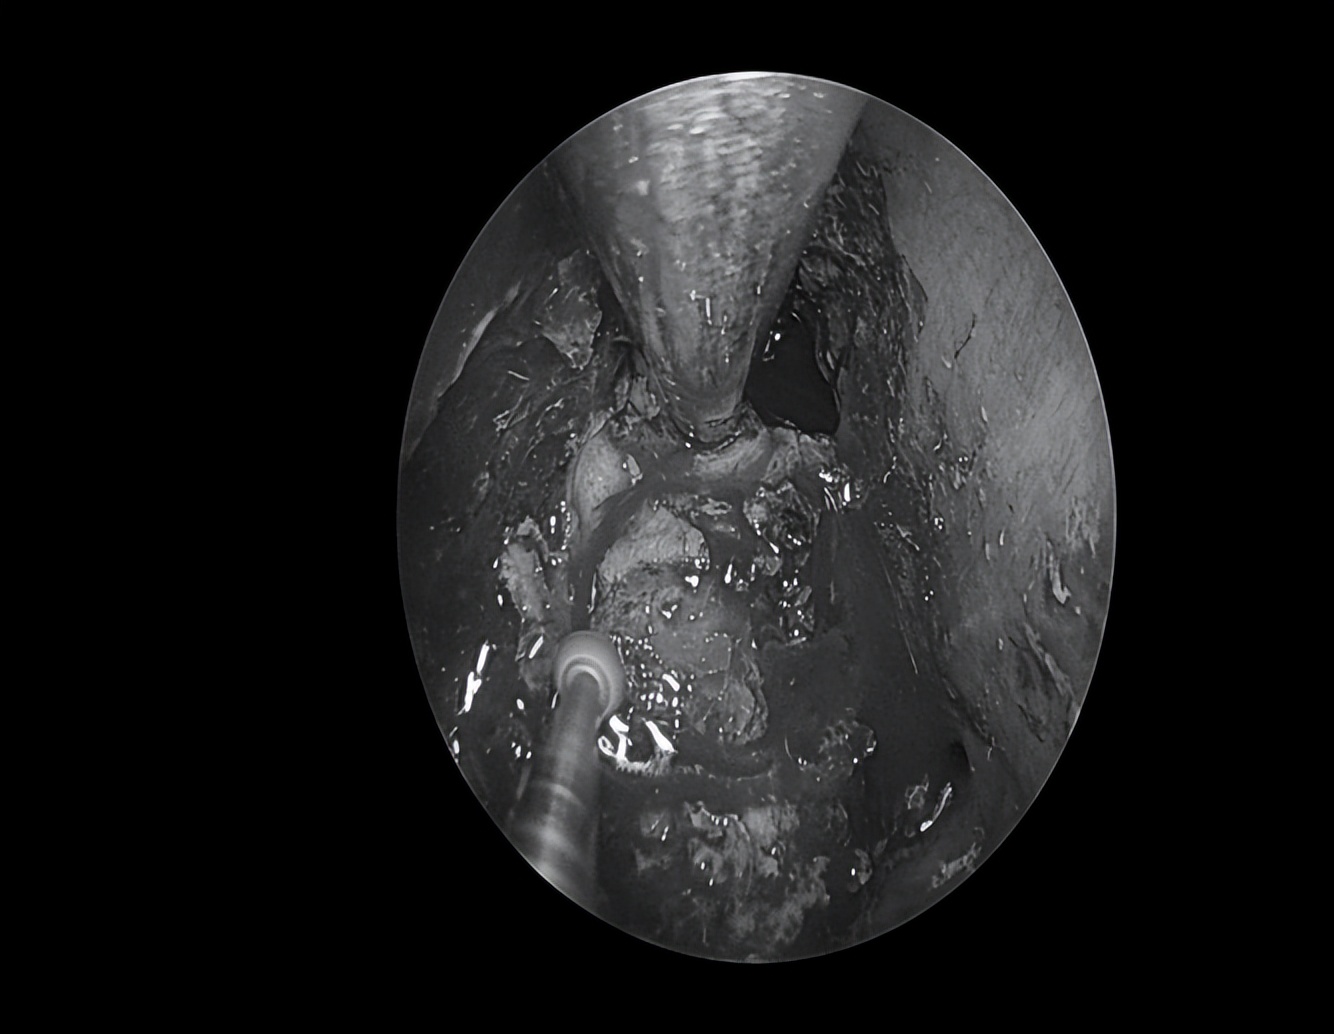

显露中颅窝底肿瘤

沿肿瘤包膜磨除肿瘤周边骨质,充分暴露肿瘤边界

切开肿瘤包膜后,可见大量豆渣样物

清除豆渣样物,显露岩骨段颈内动脉

清除囊内病变后可见中颅窝底塌陷

(星号标示处)

切除部分囊壁,清除囊内病变,充分向鼻腔开放引流